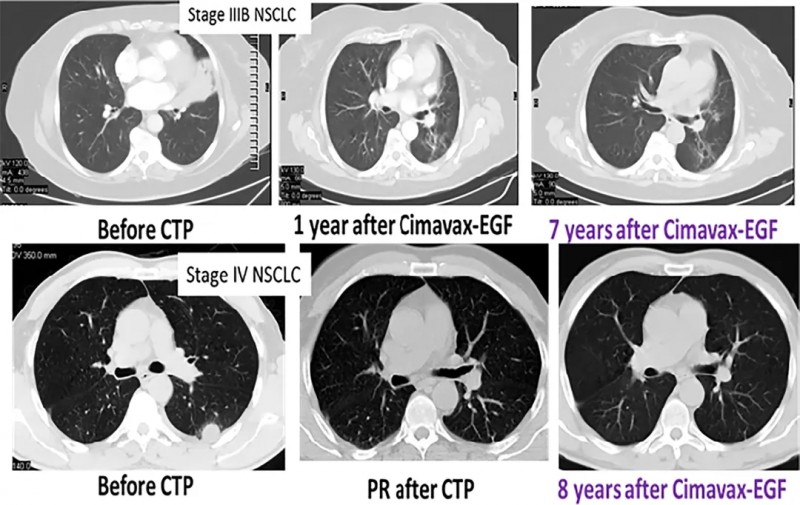

2位幸运的晚期肺癌患者接受疫苗治疗后,病情得到长期控制,截至文献发表时,已达到7年和8年,CIMAvax-EGF疫苗已经为众多晚期肺癌患者开启长生存之门。

肺癌疫苗CIMAvax-EGF是由古巴分子免疫学中心经过25年,穷尽了第一代科学家的心血成功自主研发的全球首个注册的用于晚期非小细胞肺癌的治疗性疫苗,原本是迫于美国全面封锁的就医压力,自主研发的疫苗,自给自足就够了,没想到一问世引起了全世界的轰动。目前这款疫苗已经在古巴,秘鲁,白俄罗斯等全球多个国家获批上市。近期,古巴公布了针对晚期NSCLC患者的CIMAvax-EGFIV期临床试验,这项真实世界试验表明,大约20%的患者接种疫苗超过1年或更长时间,值得注意的是,44名患者在3年或更长时间后仍接种疫苗!